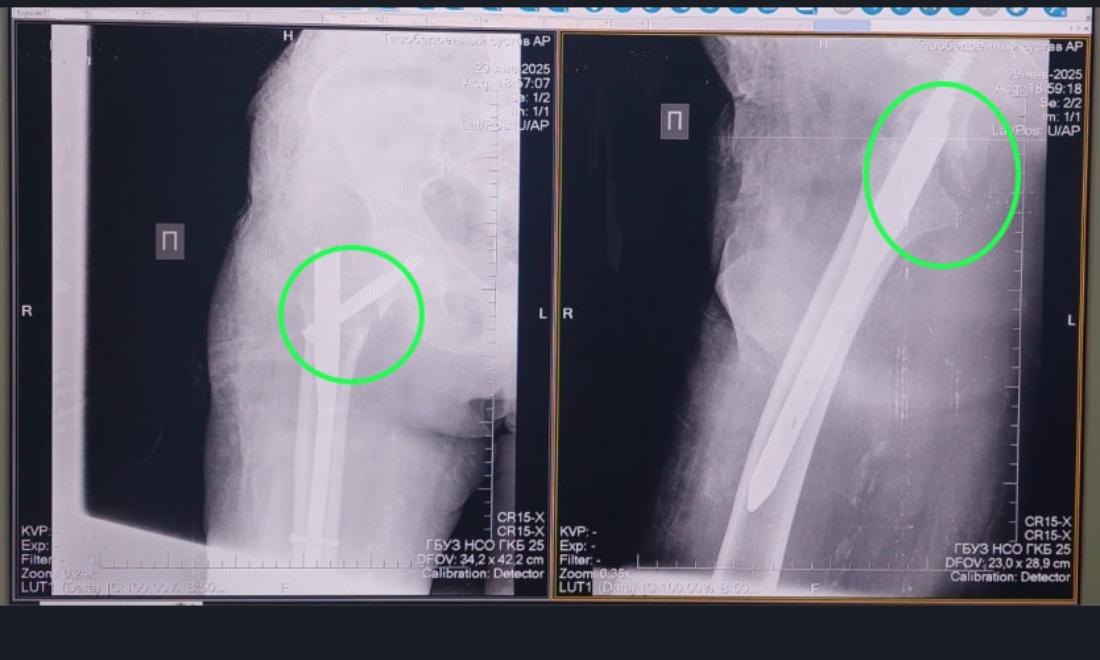

Новосибирские хирурги спасли 91-летнюю женщину с переломом шейки бедра

91-летняя жительница Болотнинского района получила перелом проксимального отдела бедренной кости. Пожилая женщина споткнулась дома о порог и упала.

Через несколько часов сибирячка поступила в Болотнинскую центральную районную больницу, оттуда её отправили в ГКБ № 25. На следующий день её прооперировали.

«В ГКБ № 25 нашей пациентке провели остеосинтез – сопоставили костные отломки и зафиксировали их металлической конструкцией. Сейчас она уже дома, перед выпиской родственники приобрели ходунки. Она уже получает дозированную лёгкую нагрузку на сустав. В таких операциях даже в 90 лет почему не отказывают? Потому что чем быстрее пациента активизировать, на ноги поставить, тем прогноз благоприятнее», – подчеркнул Абдель Таймусаев.